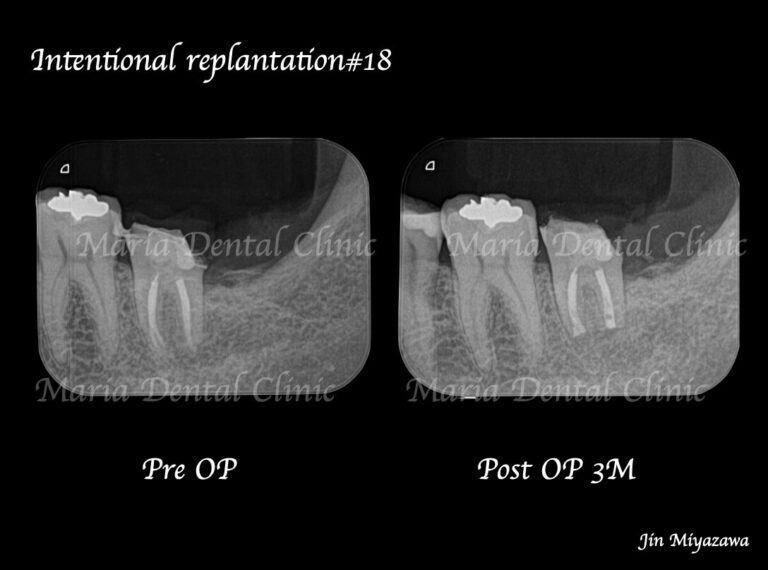

• 【症例】歯根端切除術(意図的再植術)により、病変の大きい根尖性歯周炎の抜歯を回避

• 目白マリア歯科【症例】根管治療後も症状の改善が認められないケース・意図的再植・歯根端切除術レントゲン画像術前術後

【症例】根管治療後も症状の改善が認められないケース・歯根端切除術(意図的再植術)を施し治癒へ